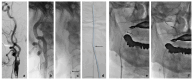

Background/Objectives: This study aimed to evaluate the incidence, risk factors, clinical implications, and rescue maneuvers of technical complications related to embolic protection devices (EPDs) during carotid artery stenting (CAS). Materials and Methods: We retrospectively reviewed all patients who had undergone CAS with EPDs between April 2018 and March 2024. The incidence and types of technical complication associated with EPDs were assessed. Clinical, angiographical, and procedural factors were analyzed to identify risk factors for the occurrence of EPD-related adverse events. Various rescue techniques for managing adverse events were investigated based on the procedure record. Results: Of the 158 enrolled patients, the rate of EPD-related technical complications was 23.4% (n = 37). Among them, complicated filter retrieval was the most common adverse event (n = 23, 14.6%). Older age, a higher degree of residual stenosis, and the type of the EPD were significant risk factors for complicated filter retrieval (p < 0.05). Although distal thrombus migration requiring thrombectomy was more frequent in patients with complicated filter removal (2.2% vs. 13.0%, p = 0.041), there was no significant increase in postprocedural thromboembolic and hemorrhagic complications. When complicated filter retrieval occurred, careful to-and-fro movement of the patients' neck, such as rotation, or asking them to swallow was tried first in all 23 patients. When these attempts failed, manipulation of a curved-tip guiding catheter, the balloon bridge technique, and alternative use of a 5 Fr angiocatheter as a retrieval sheath were sequentially tried, and all filters were successfully retrieved. Conclusions: Complicated filter retrieval was the most common technical complication during CAS. Various rescue techniques for successful filter removal were effective for ensuring safety of CAS.